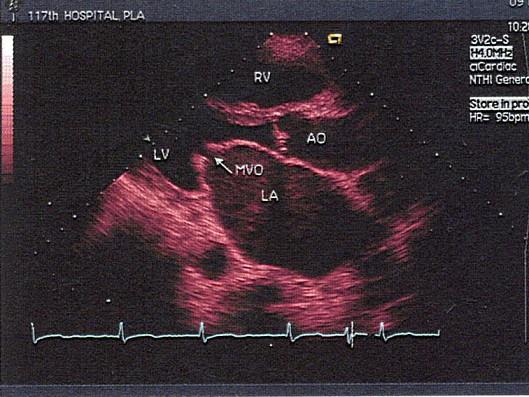

问题 该图所显示的病例为?(?)

选项 A.二尖瓣腱索断裂 B.二尖瓣脱垂 C.二尖瓣赘生物 D.风心二尖瓣狭窄 E.黏液瘤

答案 D